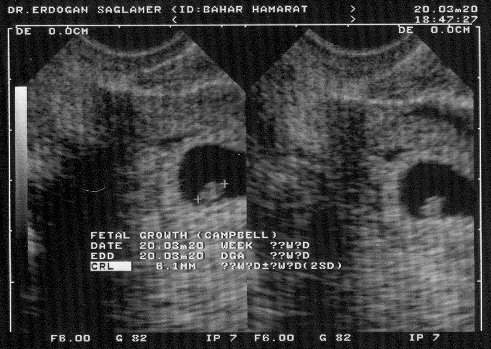

Annemle babamın beni ilk gördükleri halim.

Henüz ben "ben" değil iken...

İki "+" işareti arasında kalan 6.1 milimetrelik canlı ben oluyorum...